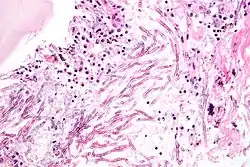

Une mycose est une infection fongique provoquée par une ou plusieurs espèces de microchampignons parasites ou saprophytes. Les pathologies fongiques étudiées par la mycologie médicale, sont souvent subdivisées en infections appelées superficielles, mycoses sous-cutanées et mycoses systémiques[1]. Elles concernent le plus souvent de petites zones de la peau et/ou des muqueuses. Beaucoup plus rarement le champignon envahit des organes internes (quand il s'agit des poumons ils peuvent y provoquer une infection évoquant une pneumonie ou une tuberculose pulmonaire).

Des microlésions de la peau ou une baisse des défenses immunitaires leur permettent de pénétrer l'épiderme puis le derme, ou des muqueuses.